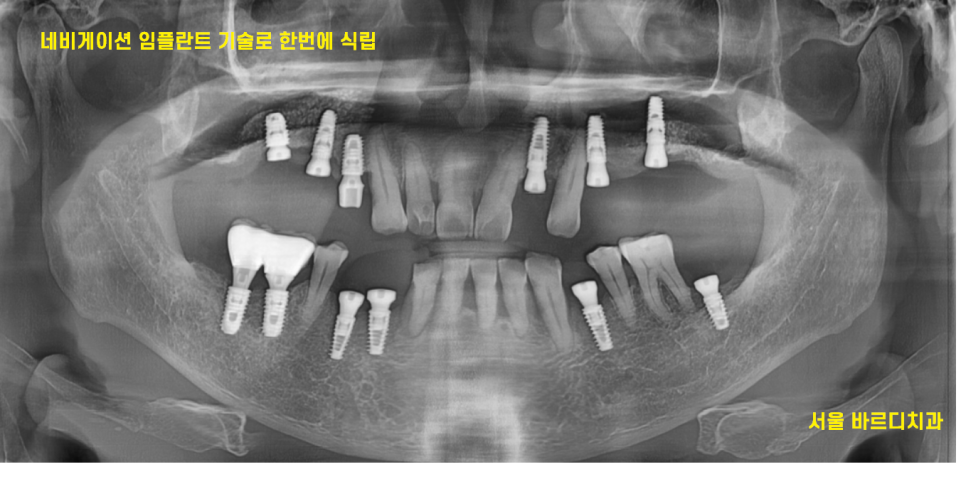

23.02.20

문제가 된 예전에 치료받은 임플란트를 먼저 제거하고

네비게이션 임플란트 수술 방법으로

치료 하기로 계획

23.02.28

ct를 통해 분석을 해보니

예전에 식립한 임플란트 3개 중

1개는 그대로 쓰셔도 되었습니다.

23.07.26

약 5개월 뒤 뼈가 충분히 만들어진 것을 확인 후

임플란트 재수술 시행하였습니다.

치아가 없던 부분도 당일 전악 임플란트를 시행하였습니다.

네비게이션 임플란트 기술을 활용하여

수술 시간은 짧고

꼭 필요한 부분만 절개하기 때문에

당일 다수의 임플란트 수술이 가능했습니다.